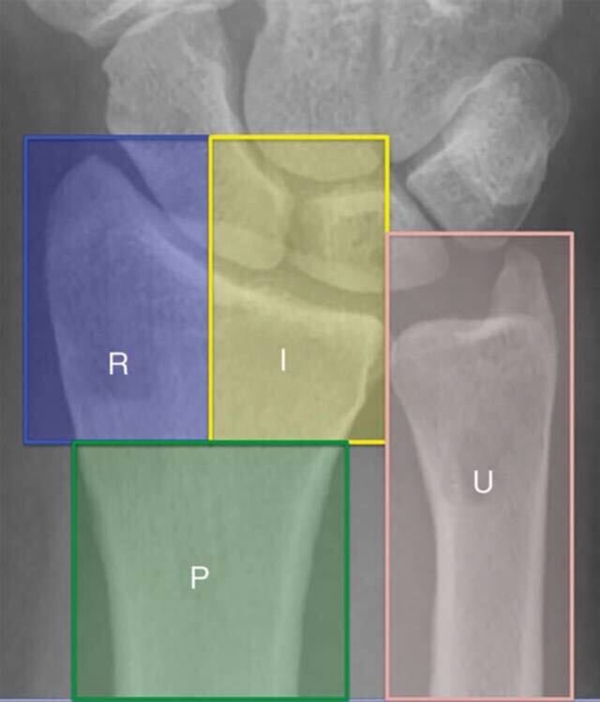

尺桡骨远端功能上分为三柱;

桡骨远端包含桡侧柱及中柱;

尺骨远端和三角纤维软骨复合体构成尺侧柱。

图1 前后位X线显示尺桡骨远端三柱结构,R为桡侧柱,I为中柱,U为尺侧柱,P为桡骨远端基底干骺端

桡侧柱的骨折常包括以较大的、骨折线累及干骺端的茎突骨块居多,肱桡肌的牵拉常导致骨折块桡侧移位和关节面移位的加重。

中柱的骨折常导致掌侧缘、背侧壁、尺背侧部分及中间游离骨块;掌侧缘骨块及尺背侧部分骨块常累及大部分月骨关节面和全部的乙状切迹,是两个关键骨块。

中柱掌侧缘骨块是桡月短韧带和掌侧下尺桡韧带止点,累及这一部分的骨折为:(1)掌屈压缩导致的掌侧不稳定伴掌侧移位、中柱短缩骨折(掌侧Batton骨折);(2)背伸压缩导致的轴向不稳定,腕骨的背侧移位,中柱背侧骨块和/或中间游离关节面骨块。

尺骨和三角纤维软骨复合体构成尺侧柱,尺侧柱是下尺桡稳定和前臂旋转运动的重要组成部分。下尺桡韧带的浅层和深层分别止于尺骨茎突尖部和尺骨小凹。桡骨远端骨折后桡骨的短缩、背侧移位和尺偏角的减小都会导致三角纤维软骨复合体和尺骨茎突的压力增加,导致继发的尺侧柱损伤。